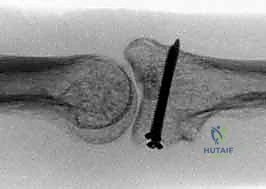

All grafts united, as demonstrated by bridging trabeculae.

Dorsal subluxation was noted in 2 of 12 patients. One was believed to have been caused by an incompetent palmar plate. The other case of dorsal subluxation was attributed to a graft that was not appropriately contoured to restore the cup-shaped geometry of the middle phalanx base.